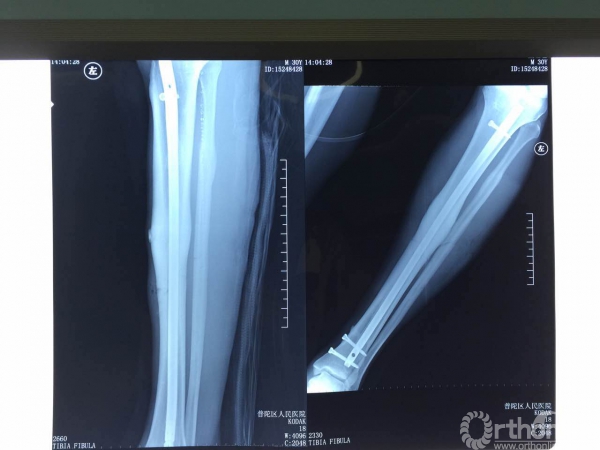

7月22日上午,万事俱备,术前计划及设备准备周全,登巴·巴在全麻下行“左胫骨髓内钉内固定术”。

正常术前准备后,手术在透视下按计划顺利进行。术中扩髓11.5mm, 使用直径10mm、长度400mm髓内钉进行内固定。由于腓骨没有移位,腓骨切开固定后有可能延长胫骨愈合时间,基于这方面担心,专家团队决定不对腓骨进行固定。为将对肌肉的刺激降到最小,专家们使用近端螺钉埋头技术,接近完美的使钉头尽可能与皮质水平。

不顾X光射线对自身的影响,专家们术中反复透视,确定螺钉位置及长短,做到每根螺钉固定都恰到好处。手术顺利,完全按照专家团队预期计划进行,结果满意,术后石膏托固定。

X光片示:固定位置好,骨折线几乎看不到。